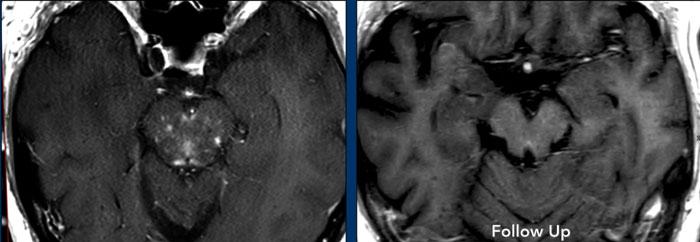

Các hình ảnh này thuộc về một nam bệnh nhân 62 tuổi nhập viện vì liệt dây thần kinh vận nhãn (dây III) bên trái.

Hình ảnh

Chuỗi xung FLAIR cho thấy tăng tín hiệu lan rộng ở cầu não và trung não.

Có hình ảnh ngấm thuốc dạng chấm và dạng tuyến tính.

Khi kết hợp các điểm ngấm thuốc ở các mức độ khác nhau, có thể nhận thấy đây thực chất là một phần của kiểu ngấm thuốc tuyến tính hoặc quanh mạch máu.

Chẩn đoán phân biệt:

- Các hình ảnh này gợi ý CLIPPERS, mặc dù đáp ứng với corticosteroid chỉ có thể được đánh giá sau khi điều trị.

Tiếp tục xem hình ảnh sau điều trị của bệnh nhân này…

Bệnh nhân này được điều trị bằng corticosteroid và hình ảnh ngấm thuốc quanh mạch máu không còn được ghi nhận trên phim chụp theo dõi.

Tiếp tục xem các lát cắt sagittal…

Trên chuỗi xung T2W lát cắt sagittal, vùng tăng tín hiệu (mũi tên vàng) cũng đã biến mất trên hình ảnh theo dõi (mũi tên xanh lá).